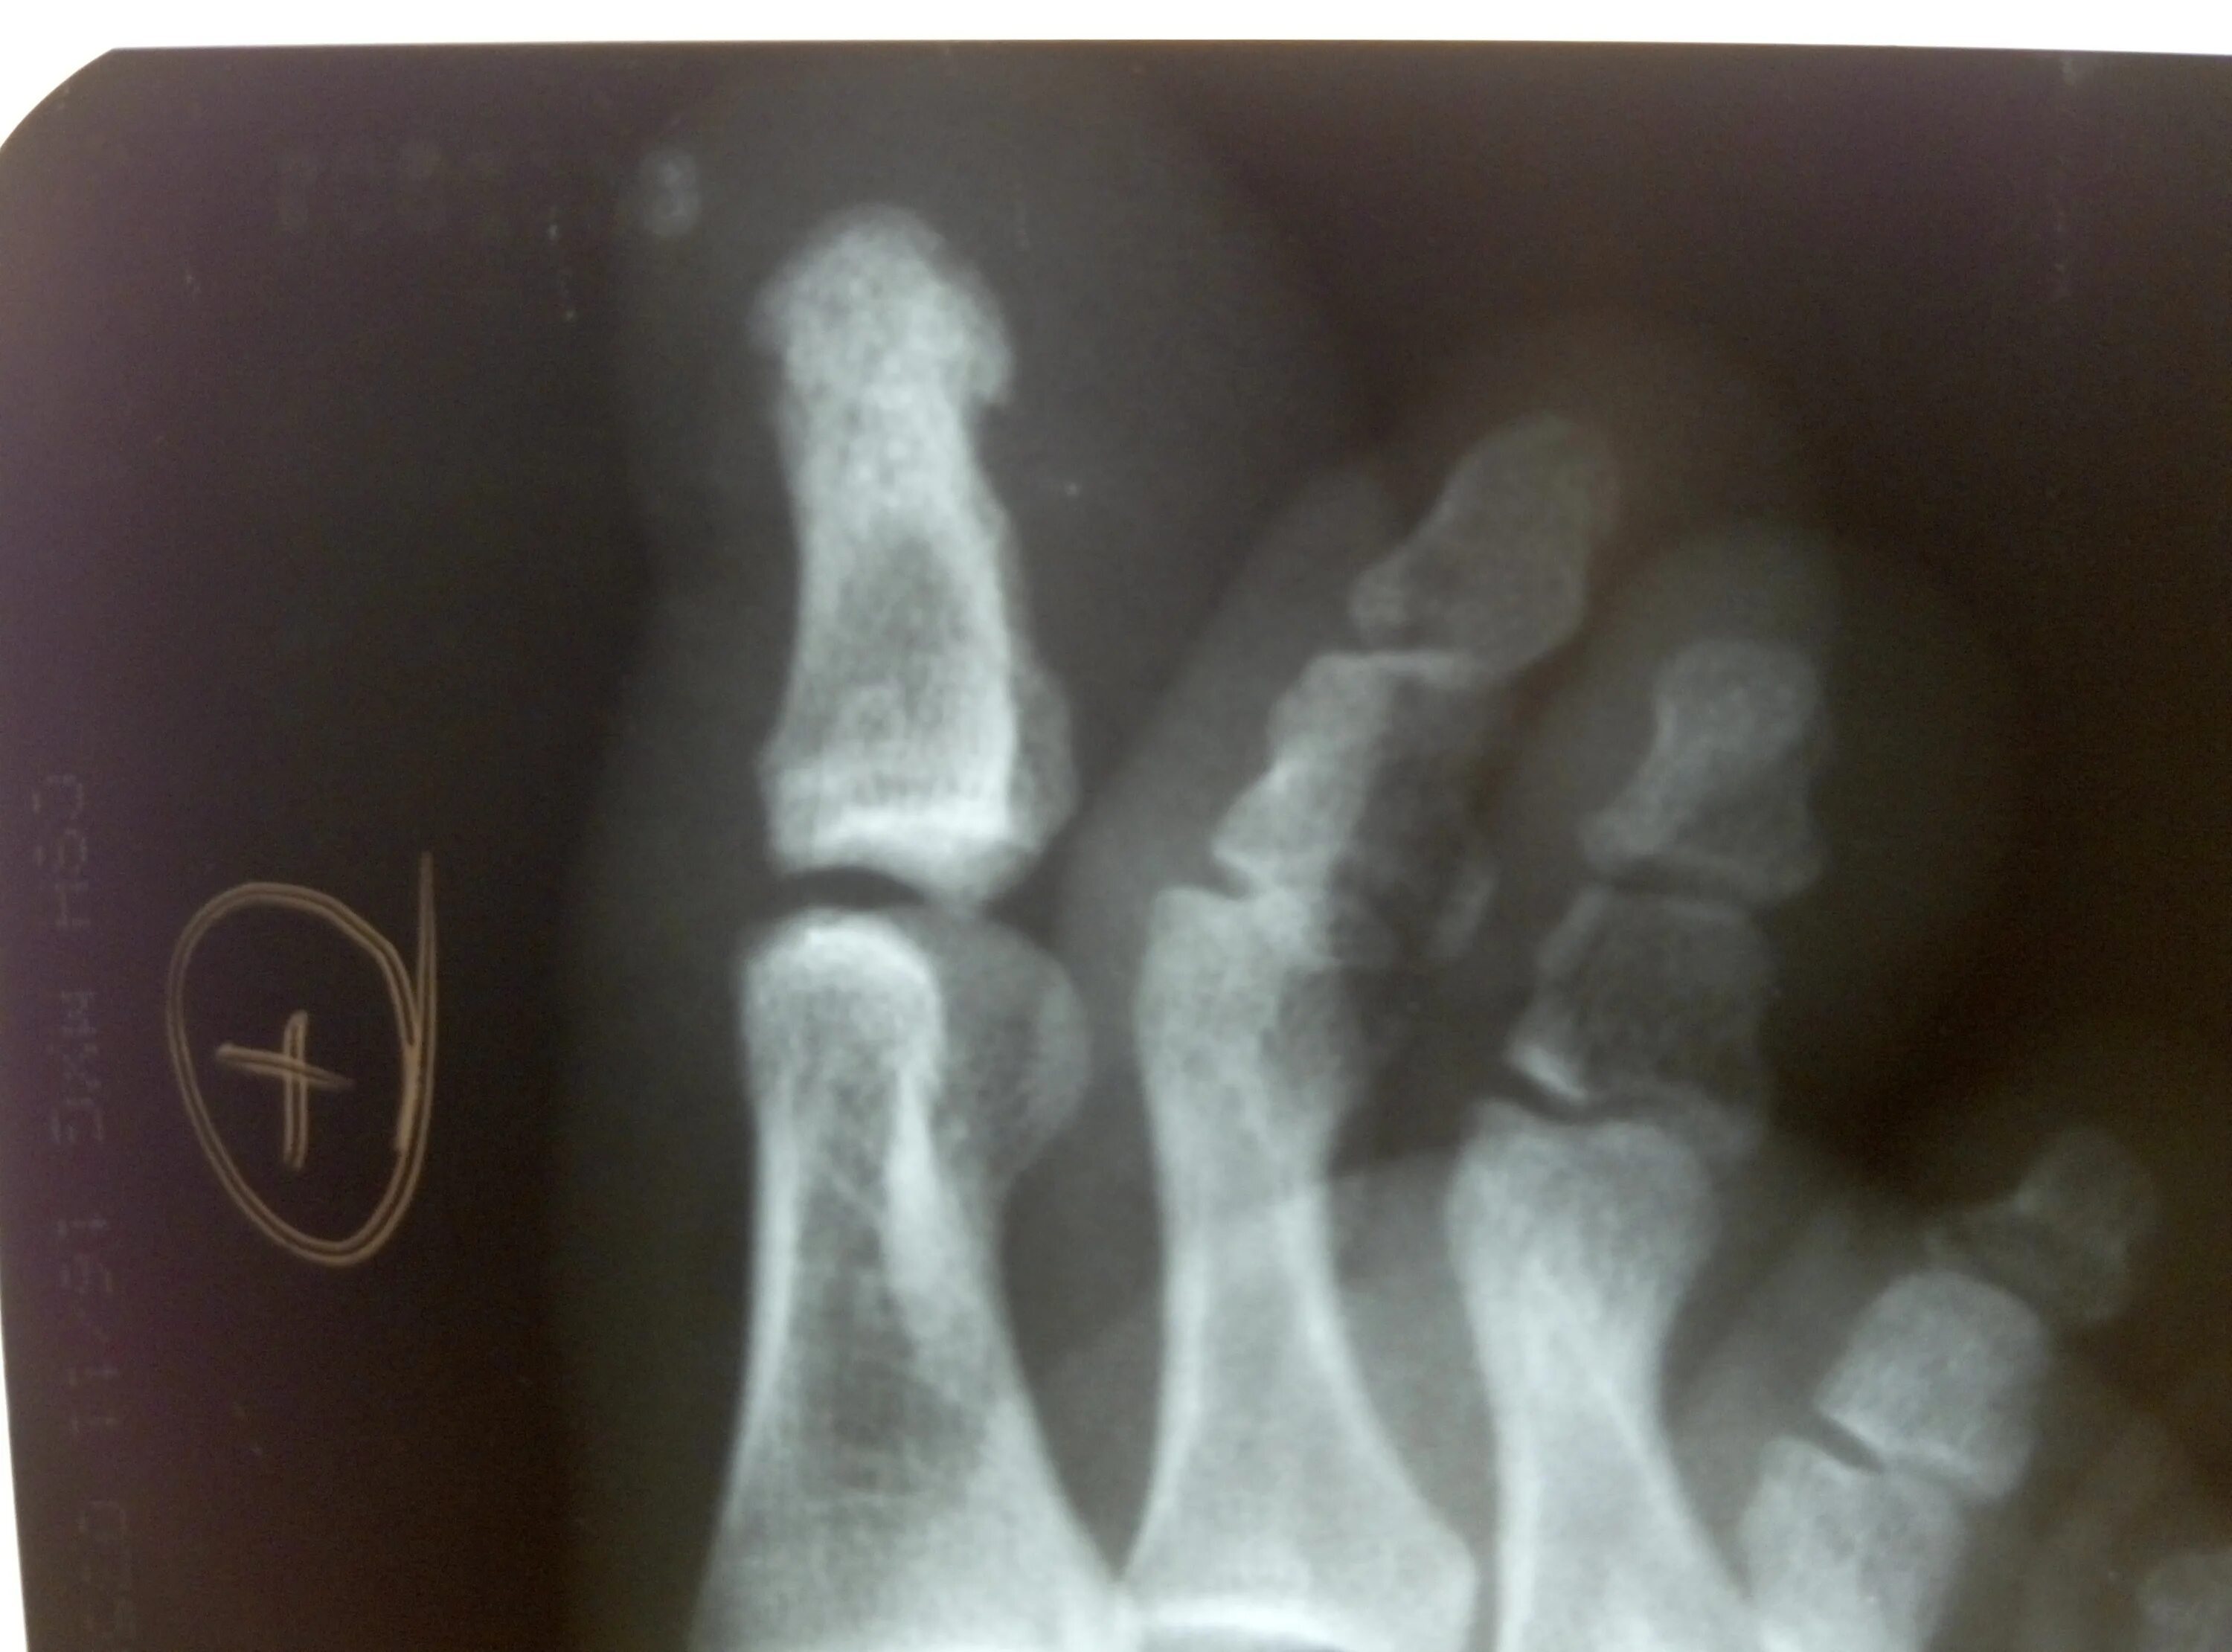

Закрытый перелом пальцев стопы мкб 10